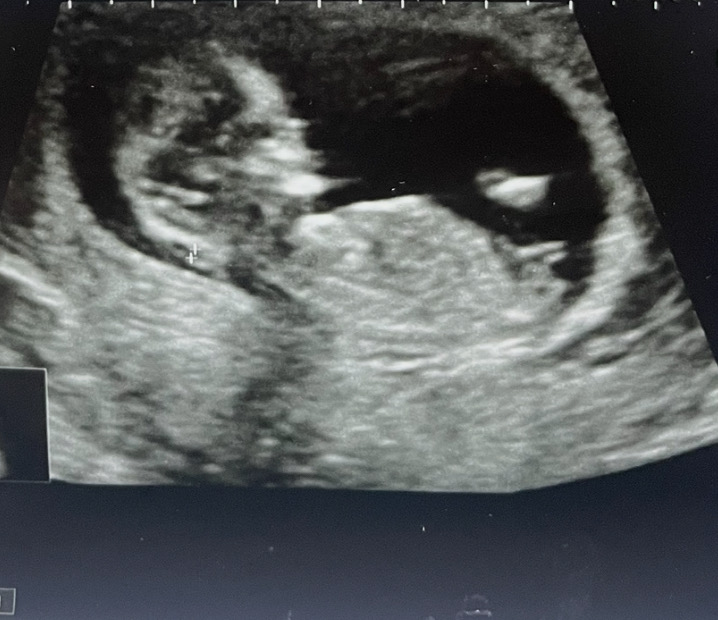

12주 각도법 궁금해요☺️

니프티해서 다음주에 성별 나올 예정이긴한데~ 각도법으로 예상되는 성별은 딸같은데..? 각도법 잘보시는분! 뭘로 보이세요?.?